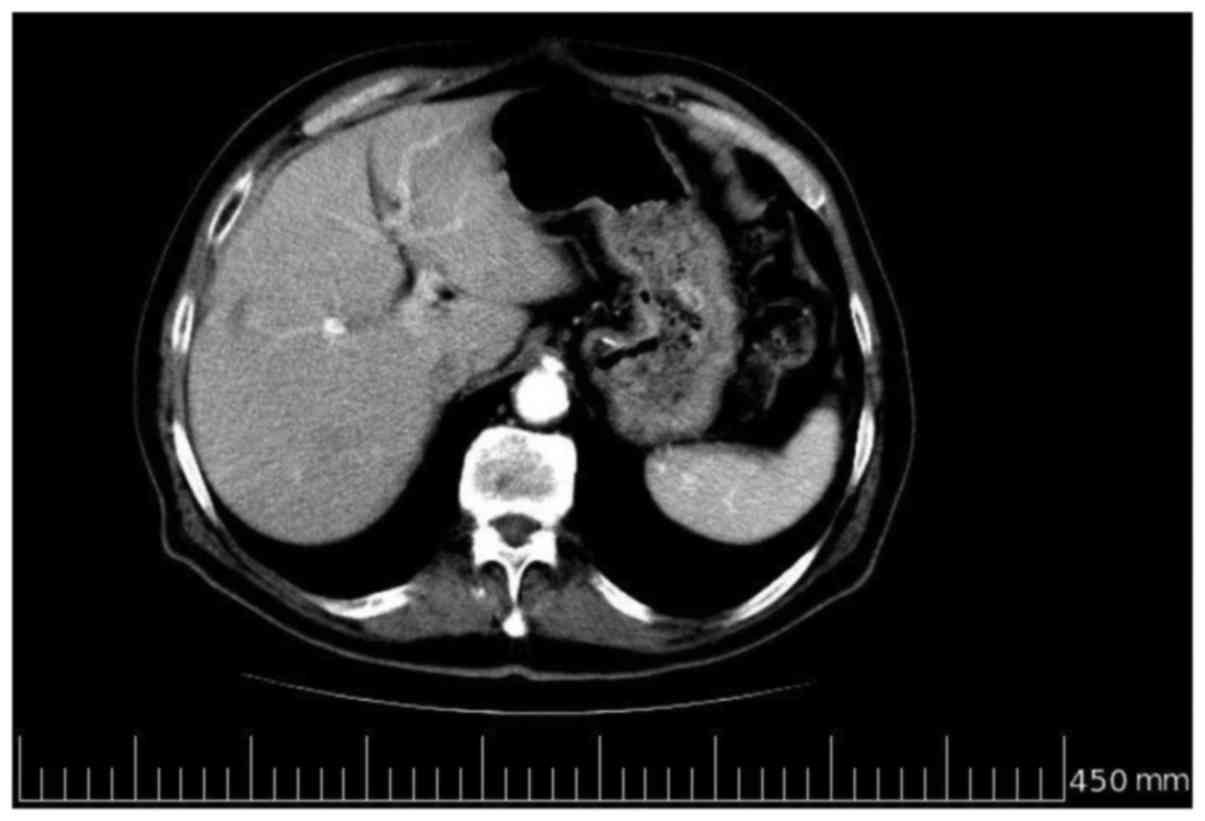

In January 2009, at the end of the sixth

chemotherapy cycle, a contrast-enhanced CT scan revealed a

reduction of >75% in the number and size of the multiple, solid

lesions evidenced in each liver lobe in the previous examinations

(Fig. 2). Further tumor marker

laboratory tests confirmed this response, indicating significantly

decreased levels compared with the pre-operative baselines (CEA,

7.2 ng/ml vs. 337.2 ng/ml; CA19-9, 7.3 U/ml vs. 109.7 U/ml; CA125,

31.3 U/ml vs. 98.2 U/ml). No hematological, gastrointestinal and/or

hand-foot syndrome toxicity was recorded. This response, in